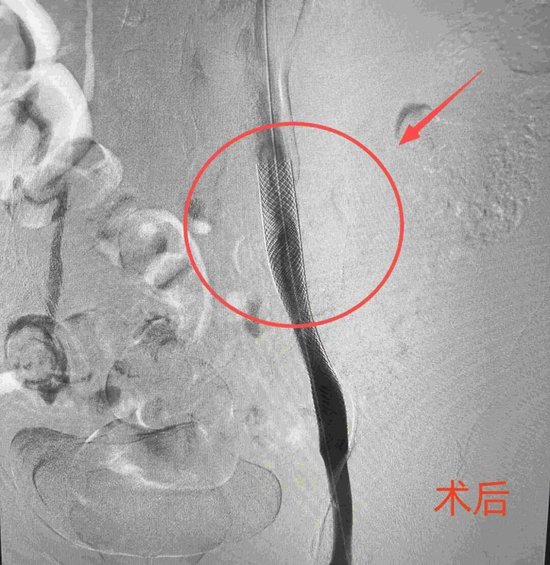

在局部麻醉下,介入科团队经右侧腘静脉成功穿刺,造影显示右髂外静脉存在约95%的极重度狭窄。团队随即对狭窄处施行了球囊扩张及支架植入术,术后造影显示支架定位精准,血流通畅,患者术前的酸胀感随之消失,手术顺利完成。